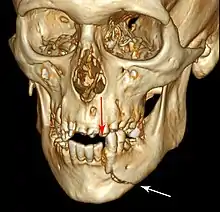

Injuries to supporting bone

This injury involves the alveolar bone and may extend beyond the alveolus.[5][6] There are five different types of alveolar fractures:

- Dentoalveolar fracture (segmental)

- Fracture of the maxilla: Le Fort fracture, zygomatic fracture, orbital blowout

- Fracture of the mandible

Trauma injuries involving the alveolus can be complicated as it does not happen in isolation, very often presents along with other types of tooth tissue injuries.

Signs of dentoalveolar fracture:

Investigation: Require more than one radiographic view to identify the fracture line.

Treatment: Reposition displaced teeth under local anaesthetic and stabilise the mobile segment with a splint for 4 weeks, suture any soft tissue lacerations.